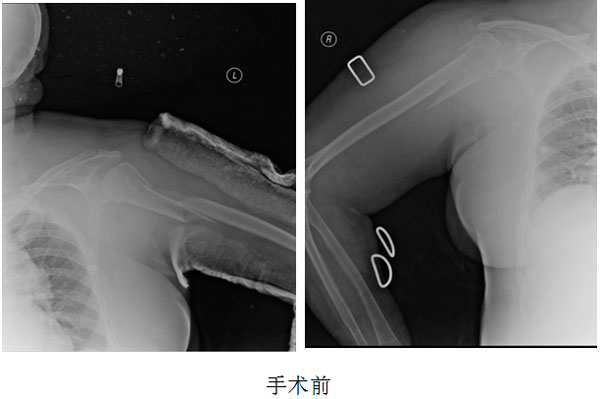

日前,我院骨科完成一例高龄老人双肱骨粉碎性骨折手术。患者,女,81岁,前几天在家不慎摔倒,致双侧肱骨近端粉碎性骨折。双侧手臂不能活动,来我院骨科就诊后,经过系统的术前检查及详细的术前评估后,为了尽快解除患者痛苦,骨科曹洪国主任决定为患者同时做双侧肱骨近端粉碎性骨折切开复位锁定钛板螺钉内固定术。

经过认真准备,手术由刘跃华与助手周宝柱、毛成与助手张猛两组医师同时进行,经过3个小时耐心细致的手术,双侧肱骨粉碎性骨折全部准确对接固定。